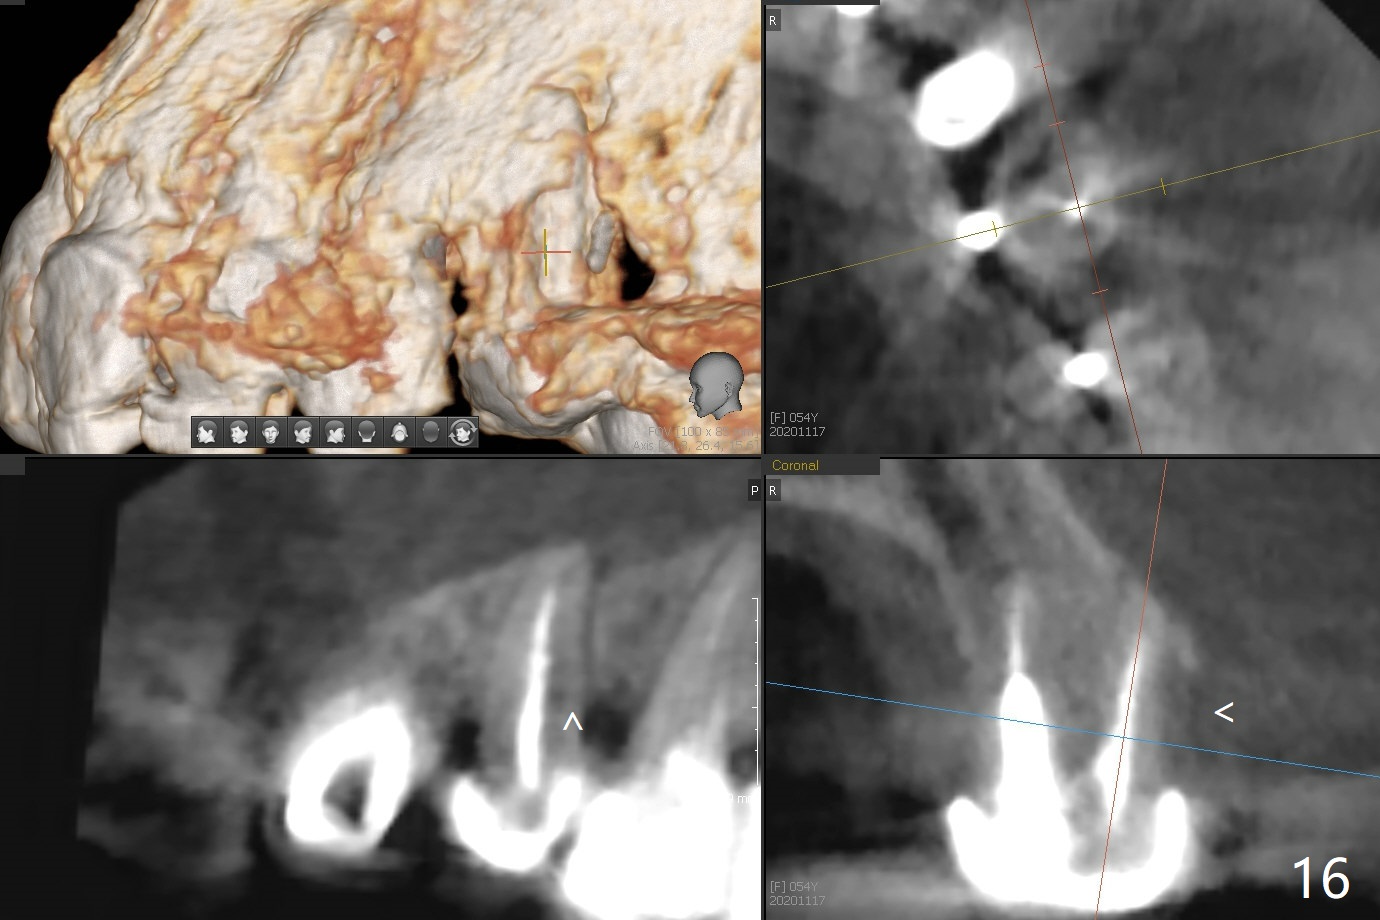

In spite of severe apical infection (Fig1,2 *), a thin narrow strip of the buccal plate (arrowheads, corresponding to the keratinized gingiva) is present when the tooth #11 is extracted. The thin bone keeps the bulging alveolus, i.e., reservoir for bone graft (Vanilla/Osteogen Fig.4 *) after placement of a 3.8x16 mm implant (Fig.3,4). A 4.5x1 mm temporary abutment, placed and trimmed for an immediate provisional, seems to be short in cuff. When an implant is placed deep to prevent periimplantitis, the cuff should be longer, i.e., 3 mm. X-ray should be taken for the depth confirmation after temporary abutment placement. Eight days postop, the mesial gingiva erythema has subsided (Fig.5 < (P: provisional)), while the apical swelling is no longer tender and most likely due to packed bone graft (*). Panoramic X-ray taken 2 weeks postop shows the clearance from the nasal cavity or the maxillary sinus (Fig.6). While the hard tissue around the implant seems to be healthy 5 months postop (Fig.7), the soft tissue is not (Fig.8). The temporary abutment is changed to a cemented one (4.5x5(2) mm) for impression (Fig.8). Since the neighboring crowns are PFM (Fig.6), the new crown will be made of the same material for shade match. Indeed PFM helps shade match in this case as well (Fig.9,10). Switching abutments (from temporary to cemented) makes it difficult to seat the crown. Post cementation X-ray leaves record for future contact loosening. The buccal gingiva remains erythematous associated with open margin (Fig.11 >) 1 year 4 months post cementation. There is no obvious bone loss 1 year 4 months post cementation (Fig.12). It appears that the crown and abutment need to be changed. Although the gingival margin remains erythematous, the gingival hemorrhage is basically lacking due to better oral hygiene during Shelter at Home (1 year 9 months post cementation, Fig.13). Change in abutment and crown will be conducted post coronavirus pandemic. In fact the abutment is incompletely seated (Fig.14 <). In addition, the tooth #12 is symptomatic with PARL associated with the buccal root (*). CBCT indicates possible buccal root fracture (Fig.15,16 ^) and loss of the buccal plate (Fig.16 <).